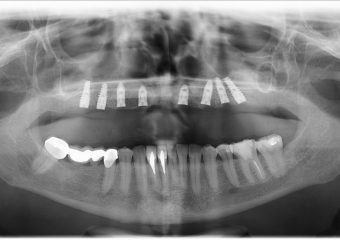

Raio - x Panorâmico Implantes

Raio-x Panorâmico com prótese provisória